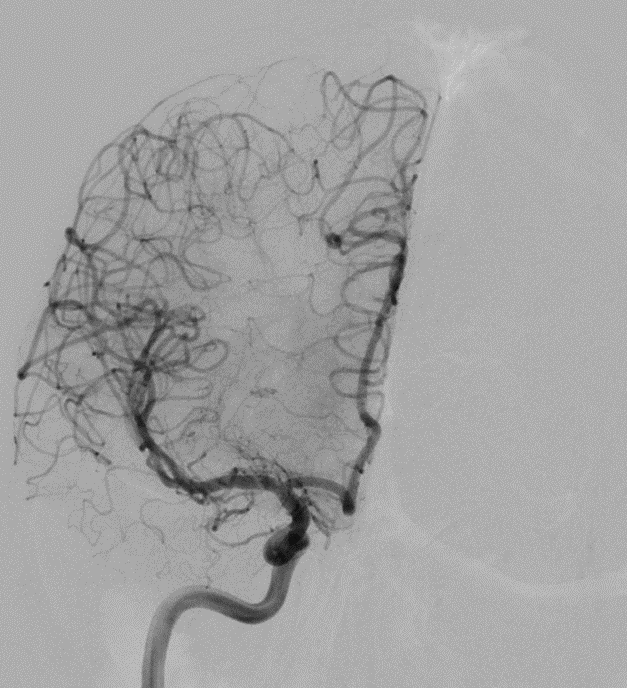

Case : AVM of leg with Pain & Limp.

Rx : AVM Embolization with Glue

#avm #embolization #irad #interventionalradiology #MedTwitter #Mumbai @ISVIRIndia @JVIRmedia @SIRspecialists @SIRRFS @cirsesociety @ApolloHosMumbai